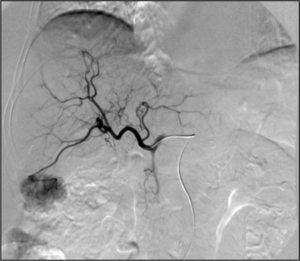

- Chemoembolization: Combined injection of chemotherapy and embolic agents into the arterial blood supply of a tumor, with the goal of both local administration of chemotherapy, slowing "washout" of the chemotherapy drug, and also decreasing tumor arterial supply

- Radioembolization: Combined injection of radioactive glass or plastic beads and embolic agents into the arterial blood supply of a tumor, with the goal of both local administration of radiotherapy, slowing "washout" of the radioactive substance, and also decreasing tumor arterial supply

- Transarterial embolization (TAE)/bland embolization: Injection of embolic material (microparticles, alcohol, glue) through a catheter into the arteries feeding a tumor to completely occlude the tumor's blood supply and cause cell death. The most common indication is for treatment of unresectable liver cancer (hepatocellular carcinoma).[68]

- Transarterial chemoembolization (TACE): Injection of a chemotherapy agent often with microparticles through a catheter into arteries feeding a tumor that both delivers chemotherapy and blocks the blood supply to the tumor to cause cell death[69]

- Selective internal radiation therapy (also known as SIRT or Y-90 radioembolization): Injection of small beads loaded with a radioactive isotope, yittrium-90 (Y-90), into blood vessels feeding a tumor to deliver a lethal dose of radiation to cause cell death.[71] Can be performed in a segmental (radiation segmentectomy) or a lobar (radiation lobectomy) fashion. Radiation lobectomy is commonly performed with the goal of inducing growth of the non-diseased lobe in order to have adequate liver function necessary to undergo surgical resection.

- Liver cancer: primary liver tumors such as hepatocellular carcinoma or cholangiocarcinoma and liver metastases are often treated by procedures such as transarterial chemoembolization (TACE), Selective internal radiation therapy (SIRT/Y-90 radioembolization), portal vein embolization, transarterial/bland embolization, or image guided ablation (RFA, MWA, IRE, cryoablation)[73]